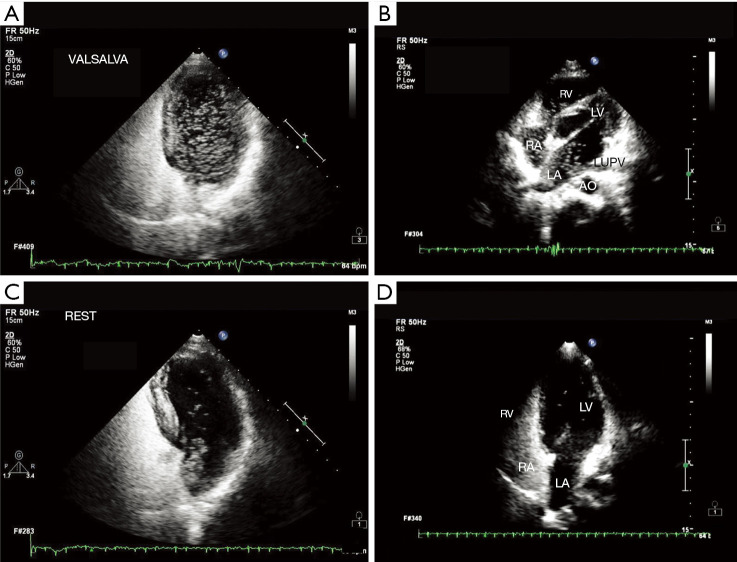

Methods: A total of 117 patients diagnosed with CS from October 2020 to June 2024 were randomly collected, and 93 patients with only headache and dizziness were randomly collected as the control group. All patients underwent agitated saline contrast echocardiography (ASCE) and the semi-quantitative classification, type and duration of RLS were analyzed. Spearman correlation analysis was used to analyze the correlation between RLS grade and type and the occurrence of CS, and the correlation between RLS duration and RLS grade and type. The efficacy of different RLS grades, types and durations in the diagnosis of CS were analyzed by receiver operating characteristic (ROC) curve.

Abstract Image